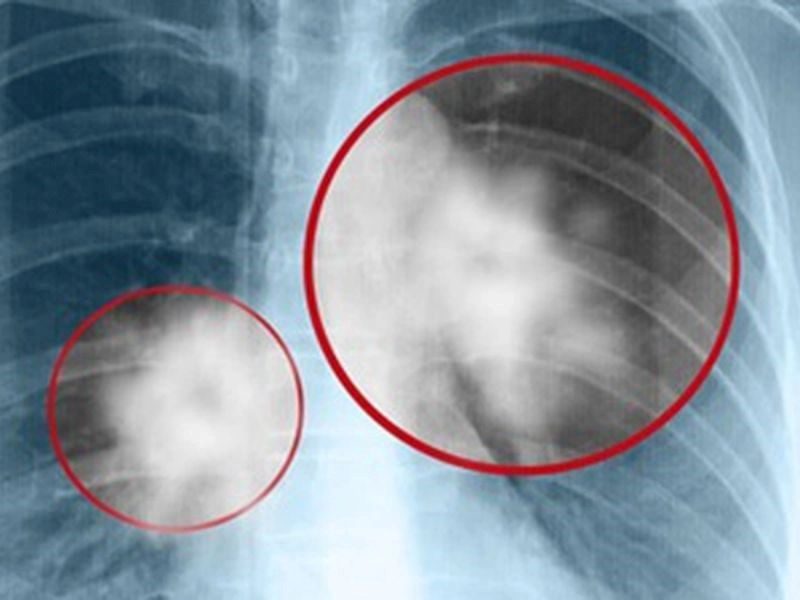

Chụp X-quang

Phương pháp chẩn đoán này hỗ trợ bác sĩ trong việc phát hiện dấu hiệu của ung thư di căn vào xương. Chụp X-quang là kỹ thuật đơn giản thường được chỉ định đầu tiên khi bệnh nhân ung thư có triệu chứng đau xương hoặc các biểu hiện nghi ngờ khác liên quan đến di căn xương. Ngoài ra, phương pháp này cũng có thể giúp phát hiện các trường hợp gãy xương do di căn.